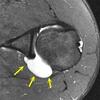

arrow demonstrates?

A, Normal infraspinatus muscle (arrow). B, Fatty infiltration of the infraspinatus muscle (arrow).